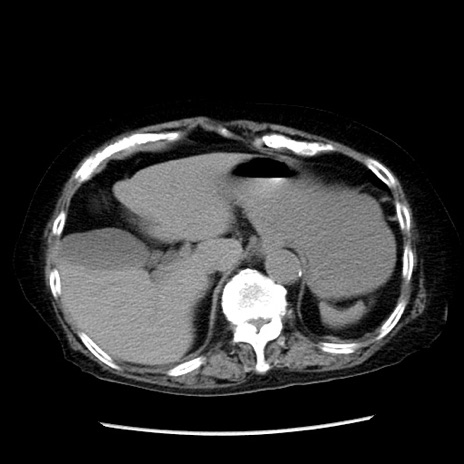

冠状断像

症例14(横断像)

【症例】 90歳代女性

【主訴】 腹痛・嘔吐

【現病歴】今朝から左側腹部痛を認めた。 経過観察していたが、嘔吐を認めたため来院。

【既往歴】 子宮癌術後

【身体所見】 意識清明、BP 127/54mmHg、P 98bpm Sp02 95%(RA)、BT 35.8°C、腹部平坦・軟腸ぜん動音聴取良好、右下腹部圧痛(+) 反跳痛なし

【データ】WBC 9800、CRP 0.46